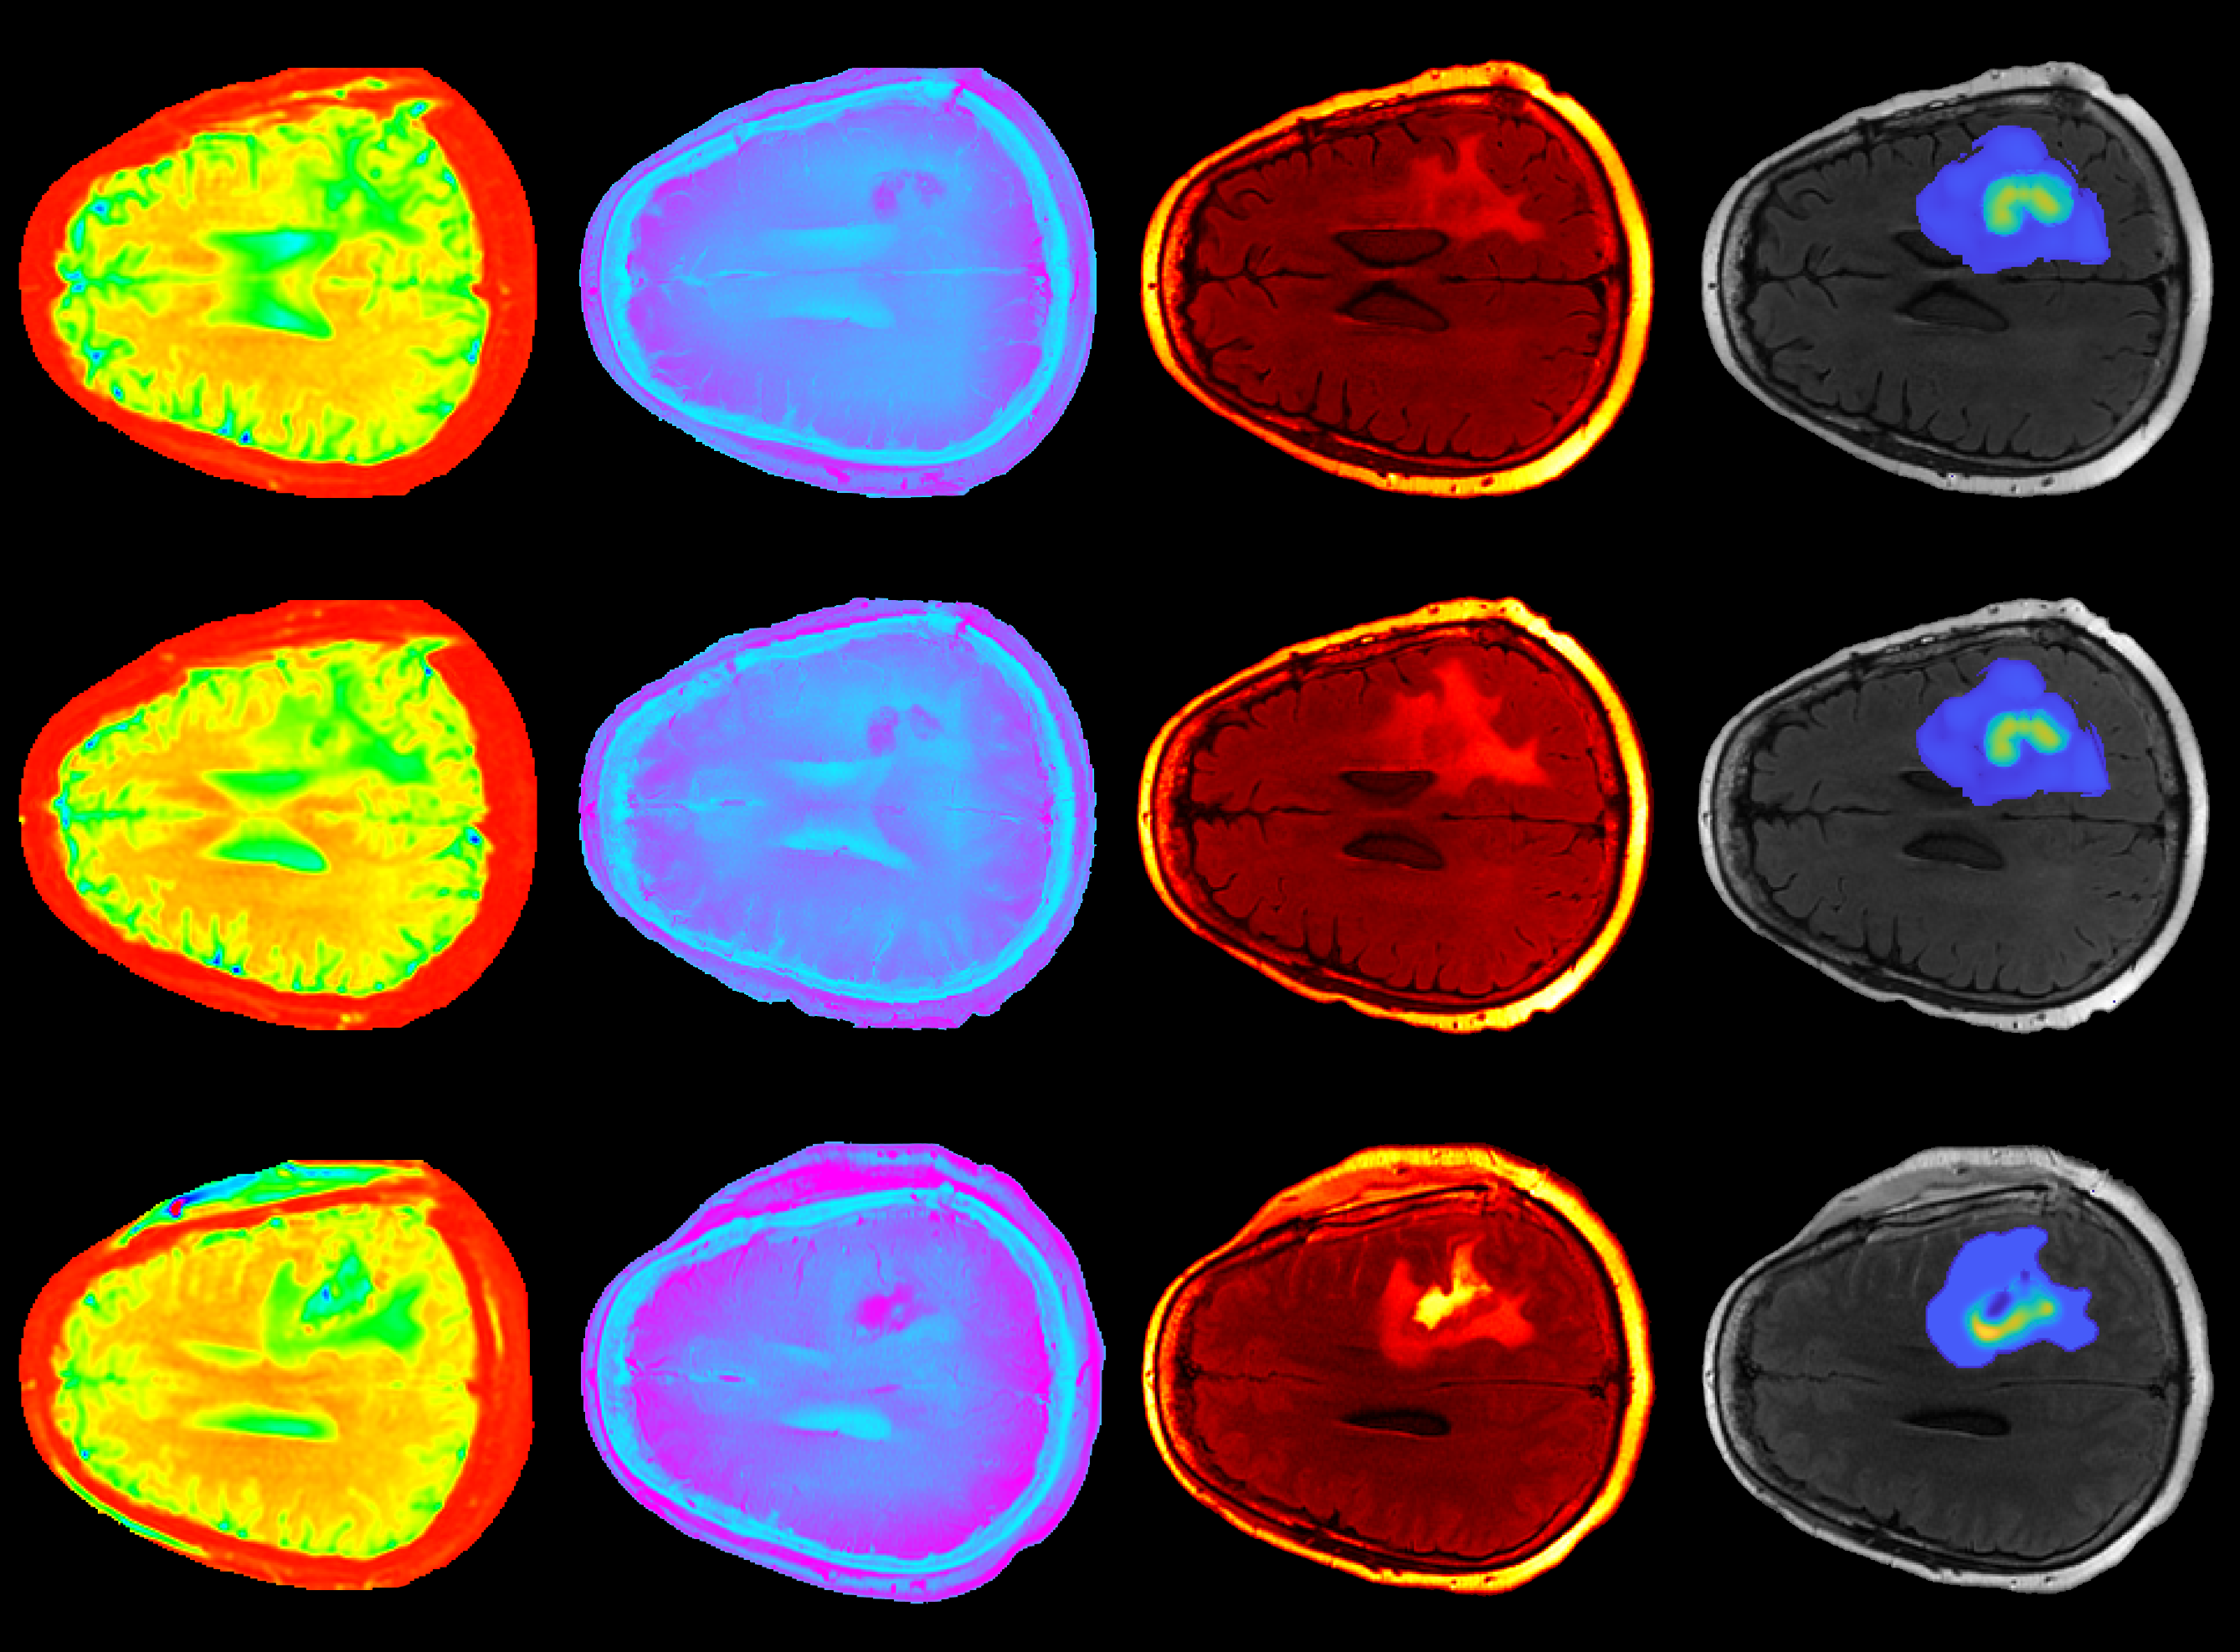

oncology

Working with partners

The University of Texas MD Anderson Cancer Center, Oden Institute’s Center for Computational Oncology, led by Dr. Tom Yankeelov, and TACC are working together to find new cancer treatments through integrating oncological data with mechanism-based modeling techniques. MD Anderson is one of the world's largest and most respected centers devoted exclusively to cancer patient care, research, education and prevention. Read more about our collaborations.